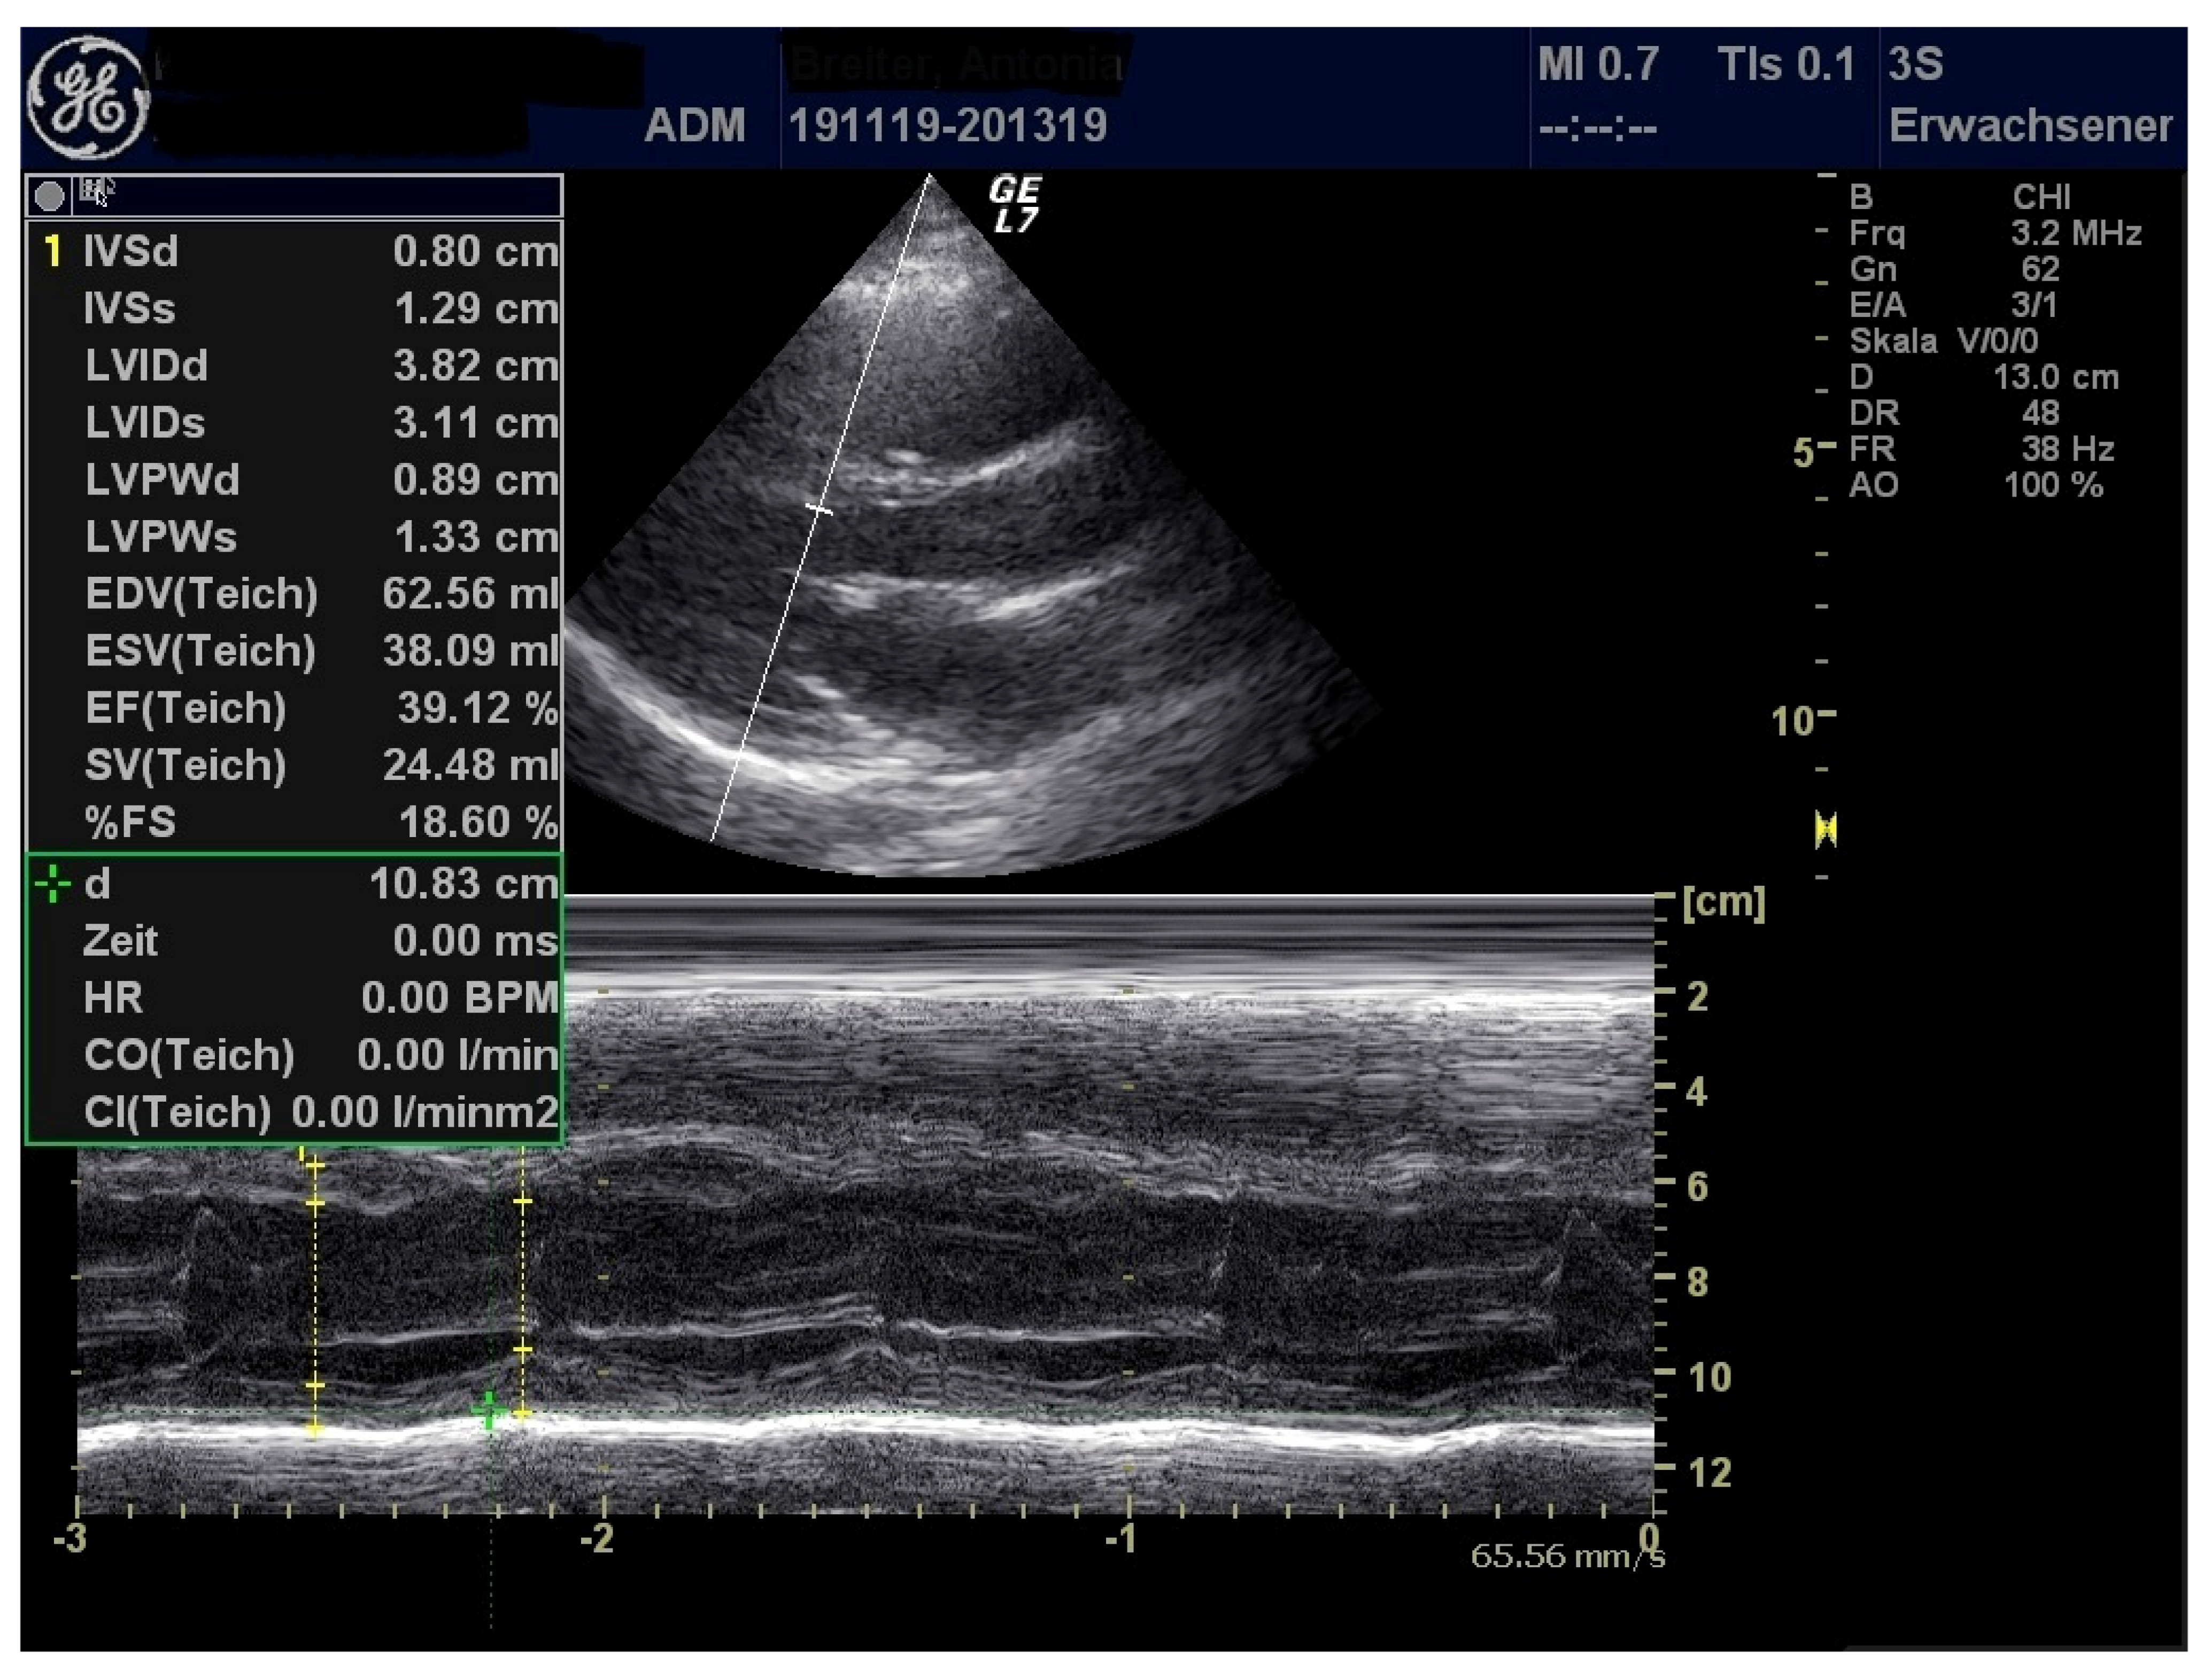

| Patient 1 | Patient 2 | Patient 3 | |

|---|---|---|---|

| LVEF (%) | 71 | 44 | 53 |

| FS (%) | 40 | 21.1 | 26.6 |

| MAPSE (cm) | 1.97 | 1.42 | 0.91 |

| TAPSE (cm) | 2.55 | 2.08 | 1.14 |

| LCA (mm) | 3.8 | 3.3 | 3.1 |

| RCA (mm) | 3.2 | 4.0 | 2.8 |

| Pericardial effusion (mm) | 7 | 3 | 5 |

| Pleural effusion (mm) | 9 (left), right 0 | 0 | 0 |